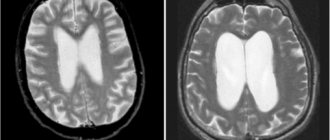

Еще одна причина, почему болит голова при давлении – нарушение движения ликвора. Это специальная жидкость, которая находится в головном и спинном мозге. Она выполняет амортизирующую функцию, защищает мягкие ткани от сдавливания и регулирует давление в черепной коробке. В норме она циркулирует постоянно, но при сосудистых патологиях, заболеваниях сердца и хронической гипертонии задерживается в головном мозге. Этот процесс сопровождается ноющей, распирающей болью, которая усиливается во время резких движений головы. Процесс опасен, поскольку в ликворе также содержатся питательные вещества для нервных клеток. Если не стимулировать циркуляцию жидкости, это может приводить к ишемии головного мозга и спровоцировать инсульт.

• МРТ головы – один из наиболее эффективных способов, который используется при подозрении на повышение внутричерепного давления, наличие новообразований и очагов ишемии;